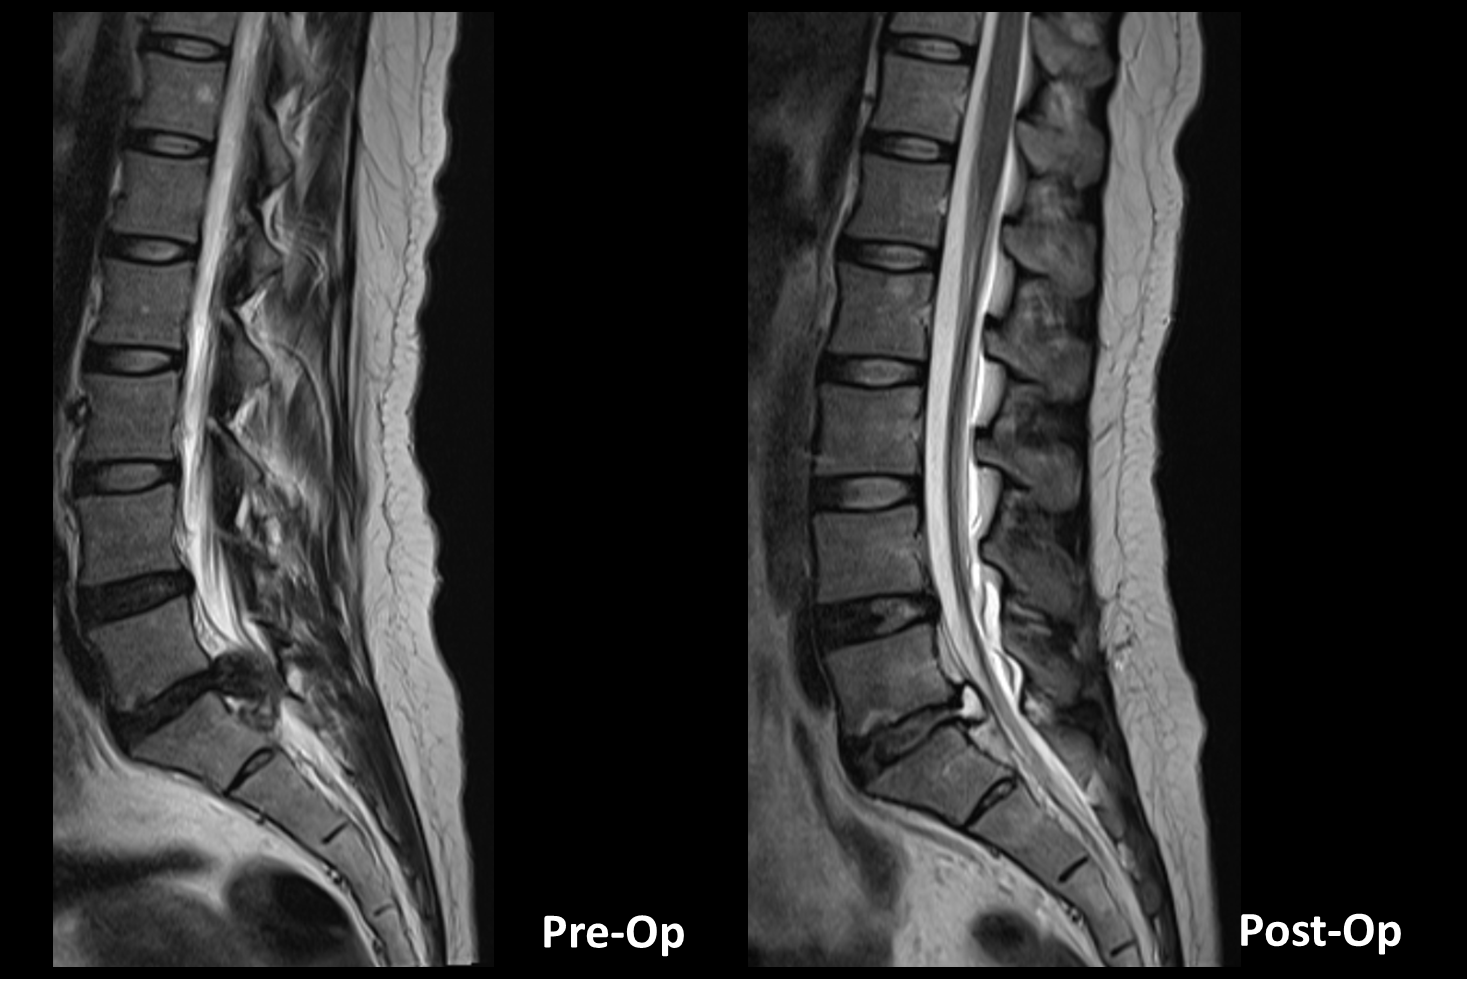

Real Patient Case

We share a variety of real spine patient cases and show you how to solve them clearly. Explore our collection of cases, where our Rationale is made clear and simple. Though this service, improve your Decision-making skills.